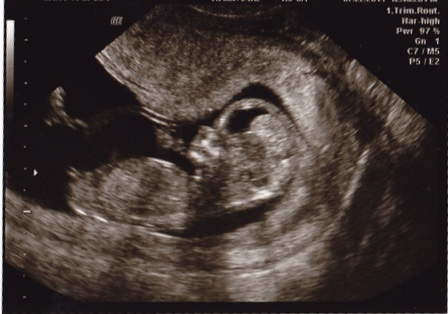

11 weeks 6 days

It looks like it is pointed up in the pic but that is only because the spine is too! Forked and parallel with spine= GIRL!

I'm useless at nubs (usually I can't even see them!) but I'm sure this is a good example of how the position of the spine can change how it looks - I can see that this nub is perfectly parallel to the bottom of the spine. Congratulations on your little girl :D

You guys are funny! You know I sort of picked the most boy looking shot because I'm paranoid. This is one out of a zillion I got plus a DVD of that session, and there are many shots where that nub looks super parallel with the spine when it's straighter. I have since actually had I think 2 more ultrasounds, and my OB even said the other day it does look just like a girl to him even though its early.

I would say boy from this shot based on angle alone. I have seen forks on both boy and girl nubs. I'm no expert though, I just spend loads of time looking at these things to get some insight on my bub's nub!!

Wow Lindi, I can totally see how that is a nub shot that could go either way ... you really do have to look at the curve of the spine like NBP mentioned, otherwise I can see where it mimics a boy nub. That's great that you've had more u/s and your OB keeps reassuring you it's a girl; I am sure if I went HT I'd be all over that too, making SURE it really is what it should be!